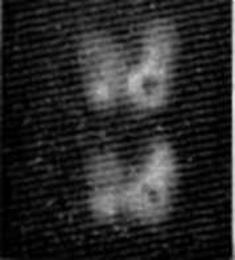

На рис. 2.4 показаны кровеносные сосуды человека в конечностях (глубоко

лежащие внутренние структуры взрослых людей оказываются слишком сложными

объектами для получения изображений с помощью существующего оборудования). Эти

картины были сняты с телевизионного устройства только что описанной системы,

когда конечность помещали в просвечиваемый ультразвуком резервуар с водой.

Рис. 2.4. Изображение, полученное с помощью

ультразвуковой голографической установки, приведенной на рис. 2.3 (С разрешения

фирмы Holosonics, Inc.).

с — раэдноенный кровеносный сосуд в верхней части рукн: б — глубокий кровеносный сосуд в нижней части ноги вблизи большой берцовой

кости.